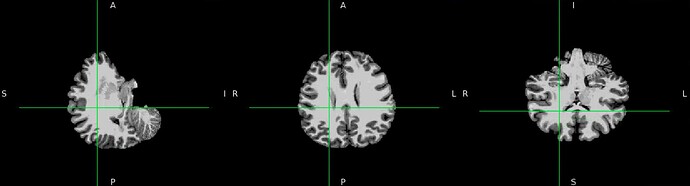

We’ve encountered a problem of misalignment between EPI and T1W. The Freesurfer bbregister failed to align EPI and T1w as well as Freesurfer mri_coreg. While the recon output seems to be alright in the fmriprep output report but it’s in a different orientation when being viewed in fsleyes. Can you kindly provide any suggestions?